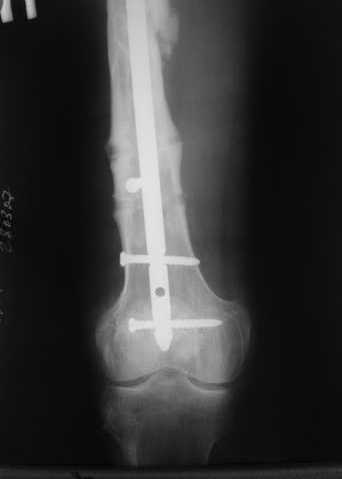

Пациенту М., 30-ти лет, 1,5 года назад в одной из московских больниц был выполнен остеосинтез бедренной кости штифтом UFN (диаметр штифта 9 мм).

К нам больной поступил с признаками ложного сустава бедренной кости, перелома

штифта и дистального блокирующего винта (images 1,2,3).